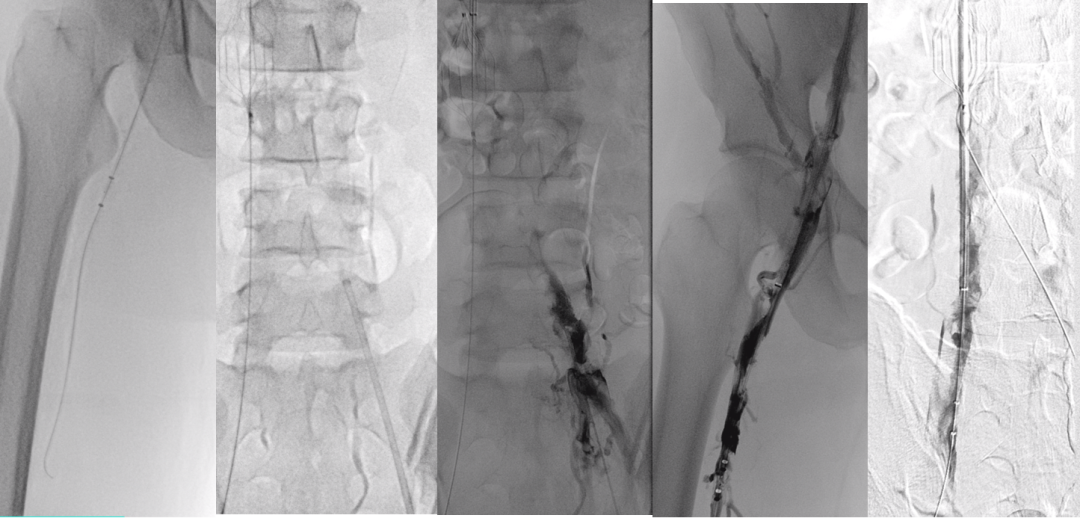

★ Case3:锥型滤器慢性腔髂静脉血栓闭塞

23M,下肢骨折合并DVT,外院放置锥形腔静脉滤器3个月,发生慢性腔髂静脉阻塞;

双下肢运动后肿胀,伴沉重感;

未规范化抗凝治疗。

图:Ⅰ期多次重复球囊扩张治疗结果

★ Case4:慢性IVCT腔髂静脉治疗

女,54岁

2024年10月22日坠落骨盆骨折,2024年11月7日置入下腔静脉滤器,11月8日手术。

2025年1月17日当地医院滤器取出术中发现下腔静脉髂静脉血栓放弃取出

图:第一次:扩张下腔静脉、髂静脉并取出滤器2025.2.13

图:二次复查CT并进行球囊扩张2025.3.31

图:早期复查结果比较满意(一年期通畅率>70%)